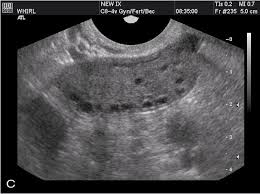

It's already a rare cancer, which makes it notoriously hard to catch. Pcos can be difficult to diagnose because some of its symptoms have a variety of potential causes. Although it's not known for sure whether benign ovarian cysts or polycystic ovaries develop into ovarian cancer, the vast majority of ovarian cysts appear to be unrelated. The reason for this is that the cysts in pcos are a cluster of simple cysts that can give the appearance on imaging as one (larger) cyst with septations. A pelvic exam, when your ovaries and uterus are checked for size, shape and consistency, can sometimes detect some reproductive system cancers at an early stage.